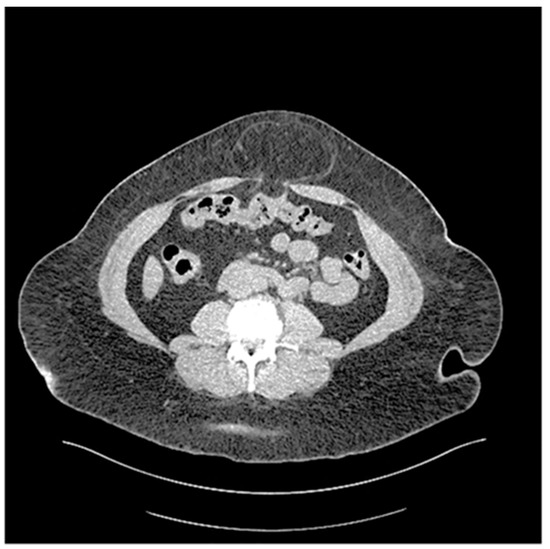

The incidence of purely acquired UH in adults is unclear because umbilical hernias, epigastric hernias, incisional hernias, and others (e.g., Spigelian hernias) are commonly grouped together (Figure 4). Small UH are unlikely to cause symptoms, and these go underreported in the literature. The coding for the procedure is variable and data is difficult to collect retrospectively from outpatient as well as inpatient settings [24]. Similarly, the number of UHR in the United States is uncertain but UHR is regularly cited as the second most common type of abdominal wall hernia repair (after inguinal hernia repair) at 255,000 in 2003. But the number of UHR has fallen recently and is now estimated to be approximately ~1,897,290 [22]. However, another small study has demonstrated an incidence of UH in up to 23–50% of patients during physical examination aided by sonography in patients who did not come with complaints of an umbilical hernia [24]. These findings underscore the difficulties in collecting precise information regarding the true incidence of umbilical hernias.

Figure 4. Abdominal wall hernias. A = umbilical hernia, B = epigastric hernia, C = Spigelian hernia, D = incisional hernia. A, B, C, and D might be all grouped at umbilical hernia. 1 = inguinal hernia, 2 = femora hernia. (Figure created by C. Phung).